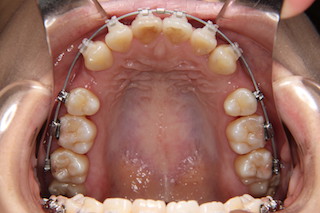

上顎・・キレイなアーチになりました!